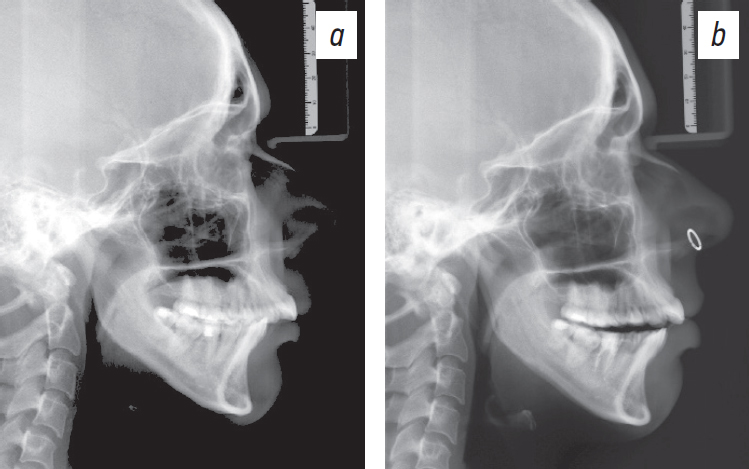

After wearing occlusal splints for 6 months (Fig. 7), a follow-up lateral cephalogram was performed. When comparing the scans, anterior displacement of the mandible was detected (Fig. 8).

Fig. 8. Lateral cephalometric radiograph: before (a) and after (b) using the mouth guard.

Рис. 8. Телерентгенограмма в боковой проекции до (a) и после (b) использования каппы.